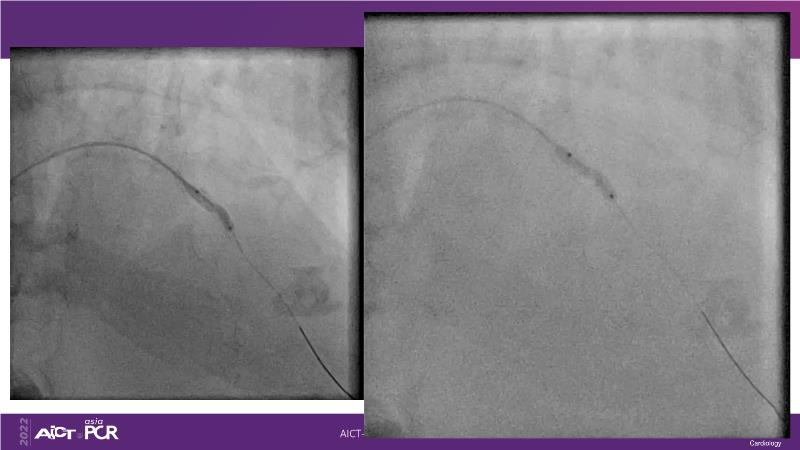

With this session, keep up to date on the evidence, trials and outcome data for intravascular lithotripsy in severely calcified lesions. Learn how to use this technique in real-world patients and understand its role in the treatment algorithm for severely calcified coronary lesions.

- To learn how to use intravascular lithotripsy in real-world patients with severely calcified coronary lesions

- To understand the appropriate role of intravascular lithotripsy in the treatment algorithm for severely calcified lesions